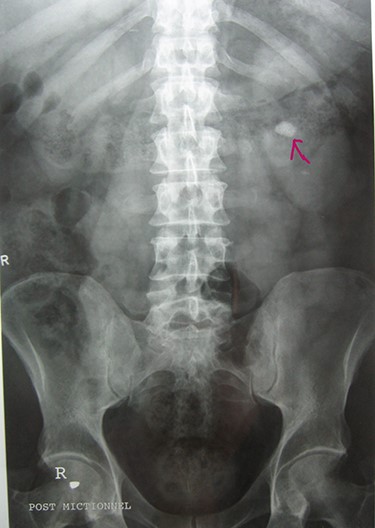

A 72-year-old man with a history of controlled diabetes and hypertension presented to our department with right inguinal swelling and intermittent lower urinary tract symptoms (LUTS) with pollakiuria, dysuria, prolonged micturition time and a sensation of a full bladder after micturition. He reported nausea, vomiting and right lower quadrant paint. The patient also reported having to manually compress the scrotum in order to empty the bladder. Physical examination revealed a slightly painful on palpation and reducible 6 cm right inguinal hernia extending into the right hemiscrotum. The body mass index of the patient was 31.4 kg/m2. His PSA was 4.3 ng/ml. On uroflowmetry, maximum flow rate (Qmax) was 13 ml/s and the voided volume was 180 cc. The uroflow curve was flat. The Bacteriological examination of urine was negative. Retrograde urethrocystography revealed right inguinal hernia containing a portion of the urinary bladder (Figs 1,2). He also had an intravenous urography in order to study the upper urinary tract and to have an idea of the renal function. This radiological exploration confirms the data of the retrograde urethrocystography and illustrates well the bladder hernia. However, a moderate left hydronephrosis with a nonobstructive pyelic calculus of 1.5 cm was observed on intravenous urography (Figs 3,4). Intraoperative findings revealed a direct right inguinal hernia with complete herniation of bladder into the scrotum. The bladder appeared healthy with no signs of injury and was restored to its normal anatomical position without resection. The hernia was repaired with a biologic mesh by the Lichtenstein technique. The patient had an uneventful postoperative course. Concerning his pyelic calculus problem, shock wave lithotripsy sessions were scheduled.

Retrograde urethrocystography: right inguinal hernia containing a portion of the urinary bladder.

Urethrocystography: no obstruction under the bladder in the per mictional image.